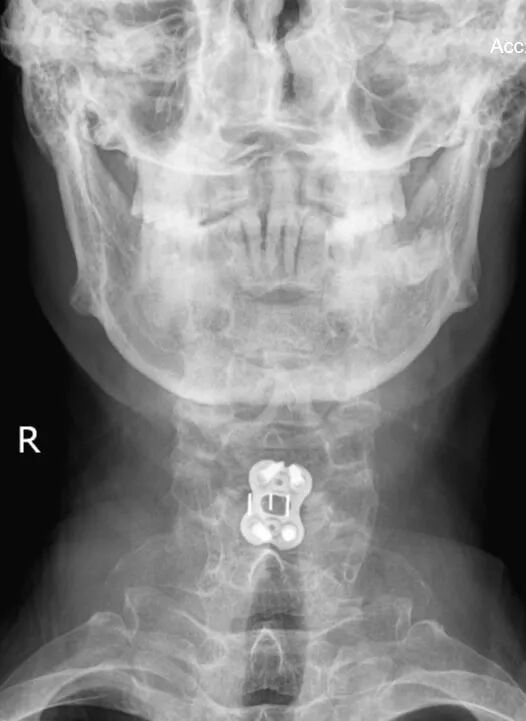

立即安排颈椎MRI检查让病灶“无所遁形”

检查结果实锤!李先生颈椎椎管狭窄、脊髓受压明显,确诊为脊髓型颈椎病——颈椎病里的“狠角色”!

颈前路髓核摘除椎管减压、椎间植骨融合内固定术